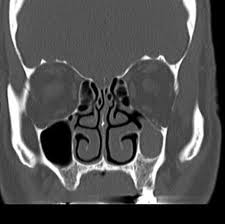

The visual sign of silent sinus syndrome is the asymmetry of the face and the asymmetry of face may lead to many other problems like diplopia. Recent findings Silent sinus syndrome lies on a spectrum of other forms of sinus-related orbitopathy. Radiographic features of disease include an opacified and hypoplastic sinus a lateralized uncinate process depression of the orbital.

The first case of maxillary sinus opacification and atelectasis was reported by Montgomery in 1964 It was not until 30 years later however that the term silent sinus syndrome was attributed to this phenomenon Patients typically present with unilateral painless enophthalmos and hypoglobus progressing over a period of several months. The silent sinus syndrome is characterized by painless enophthalmos associated with involution of the maxillary sinus after infundibular occlusion 12345678910. The hypoventilation over time results in resorption of.

Silent sinus syndrome is rare and multiple findings are needed for the diagnosis. The hypoventilation over time results in resorption of. Diplopia is seen in about 28 to 65 of cases regarding silent sinus syndrome. Silent sinus syndrome is more common in patients in their 30s and 40s ranging from 19 to 82 years mean 39 without gender or laterality bias. These include enophthalmos or hypoglobus in the absence of clinically evident sinonasal inflammatory disease. The first case of maxillary sinus opacification and atelectasis was reported by Montgomery in 1964 It was not until 30 years later however that the term silent sinus syndrome was attributed to this phenomenon Patients typically present with unilateral painless enophthalmos and hypoglobus progressing over a period of several months. 5 The proposed mechanism for the development of silent sinus syndrome is a hypoventilated maxillary sinus from an obstructed ostiomeatal complex. The silent sinus syndrome is a spontaneous unilateral maxillary atelectasis with complete or partial opacification of the sinus. The silent sinus syndrome is a rare clinical entity of spontaneous enophthalmos and hypoglobus caused by an alteration of the normal orbital architecture and function from maxillary sinus collapse in the setting of chronic sinusitis.

When looking at all the pictures on google the symptoms its all matching. Ocular motility limitation also occur and sometimes reported along with hypo Globus. Silent sinus syndrome is more common in patients in their 30s and 40s ranging from 19 to 82 years mean 39 without gender or laterality bias. Silent sinus syndrome is usually diagnosed in patients in their 30s and 40s with a mean age of 39 and a range of 19 to 82 11. Radiographic features of disease include an opacified and hypoplastic sinus a lateralized uncinate process depression of the orbital. Uncommon presentations and descriptions of sinus involvement other than the maxillary sinus add to the variability of presentation. These include enophthalmos or hypoglobus in the absence of clinically evident sinonasal inflammatory disease.